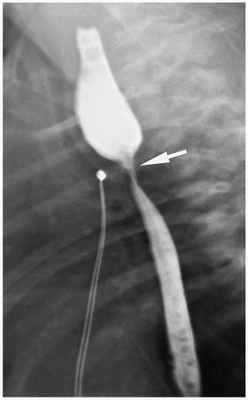

Также проводится рентген-контрастное исследование. Через зонд в верхний сегмент пищевода вводится не более 1 мл контраста. При наличии верхнего трахеопищеводного свища, кроме пищевода окрашивается ещё и трахеобронхиальное дерево.

Для диагностики стеноза пищевода проводится фиброэзофагоскопия и рентгеноскопия пищевода. Рентгенологическими признаками стеноза являются сужения в области зоны анастомоза и расширение пищевода выше анастомоза, отмечается замедление прохождения контрастного вещества за зону анастомоза. Если сужение пищевода всё-таки обнаружится, что в пищевод будет вставлена специальная трубка — буж, которая будет поддерживать канал в расширенном состоянии [1] [4] [11] .